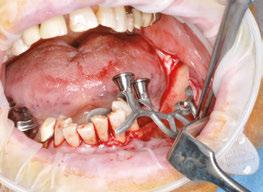

The procedure begins with local anesthesia at multiple points, vestibular and lingual, from the symphyseal region to the ascending ramus. However, an infiltration in the lingula of the mandible is not necessary. The incision is performed using the technique described above (Figures 5A and 5B).

It is imperative to carefully reflect a full-thickness flap following the periosteum. After reflection, an atraumatic periosteal expansion using a soft brush (Figure 6) will allow for the flaps to be repositioned without tension over the implant and bony surfaces at the end of the procedure.

Figures 8A-8D: Placing the subperiosteal implant and monitoring its adaptation Figures 5A and 5B: 5A. Initial clinical view. 5B. Access flap Figure 6: Periosteal expansion using a soft brush Figure 7: Prehension of the subperiosteal implant

After the soft tissue is prepared, the bony surface is carefully cleaned. For easy insertion, the healing abutments are left in place, and the implant is held firmly with hemostatic forceps (Figure 7). The implant is inserted via distal translation in the direction of the angle of the mandible, then a mesio-anterior rotation. The surgeon must control the lack of mobility and the adaptation of the implant to the bony surface at all points (Figures 8A, 8B, 8C, and 8D).

To ensure the implant is stable during the osseointegration period, an osteosynthesis screw is placed in the prepared space (Figures 9A, 9B, 9C, and 9D).